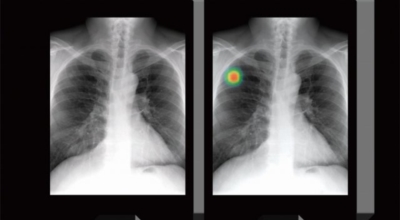

폐암 검사는 X-ray를 통해서 검사하는데 , 크기가 작거나 구석에 위치한 경우 확인이 어려운 경우도 있답니다. 그리고 조직 검사를 통해서 정확한 진단을 하게 돼요. 폐암이 발견되면 종양의 크기나 전이 여부 , 위치에 따라서 수술 여부를 결정하게 돼요.